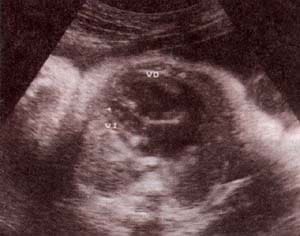

fig. 62. – (a). 18 semanas.corte sagital. |

fig. 62. – (b). corte transversal. estas formas de inicio precoz se hallan con frecuencia asociadas a anomalías cromosómicas. |